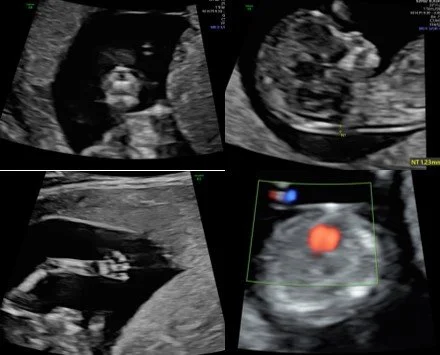

SIÊU ÂM HÌNH THÁI HỌC QUÝ 1

-         Đo độ mờ da gáy để tính nguy cơ mắc các hội chứng di truyền

Loại siêu âm này được thực hiện ở tuổi thai 11 tuần đến 13 tuần 6 ngày (chiều dài đầu mông từ 45-84mm) và có thể kết hợp với đo đạc phổ Doppler động mạch tử cung để đánh giá nguy cơ thai phụ mắc tiền sản giật sau này. Đây là một loại siêu âm quan trọng trong thai kì vì vượt quá mốc tuổi thai này thai nhi sẽ không đo được độ mờ da gáy (một thông tin cực kì hữu ích trong quá trình sàng lọc tiền sản). Ngoài ra ở giai đoạn này thai nhi đã có gần đủ các cơ quan và một số dị tật lớn đã có thể phát hiện ở giai đoạn này và một số nghiên cứu gần đây cho thấy độ nhạy để phát hiện dị tật lớn ở giai đoạn này có thể đạt tới 30 - 50% [1,2,3].